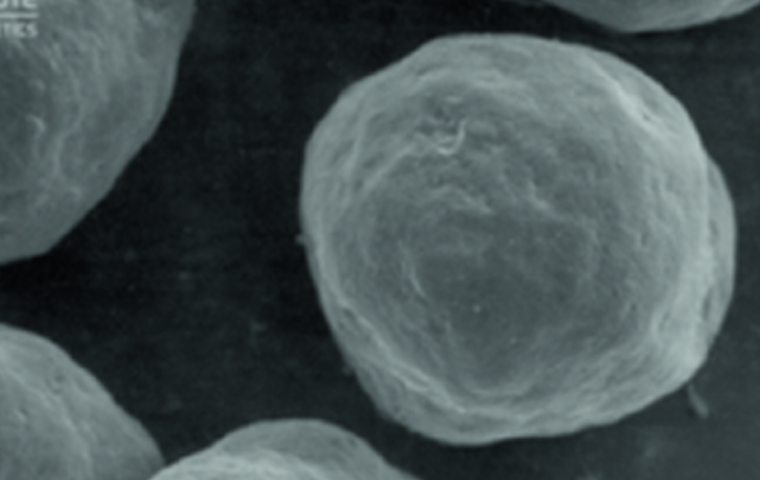

수용성 겔 캐리어와 미세한

CaHA(칼슘 하이드록시아파타이트) 입자로

구성된 칼슘 미네랄 필러입니다.